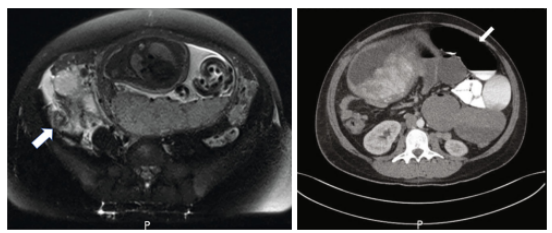

图1. 在T2加权MRI上发现急性阑尾炎。右下象限阑尾扩张(箭头),周围有炎症改变

图2. CT显示小肠梗阻。近端小肠严重扩张(箭头所示),直径达6 cm,子宫穹顶后中腹小肠突然变细

在35 4/7周时患者因弥漫性腹痛再次到医院就诊,发现部分小肠梗阻。在与普通外科会诊后,患者接受了保守治疗。在住院第二天,肠功能恢复,出院回家。一周后,在36 4/7周时,患者表现为腹痛、恶心和呕吐,并连续几天没有排便。再次被诊断为小肠梗阻,经CT证实(图2)。考虑到患者的生命体征稳定,决定继续保守治疗。随后,患者通过阴道成功分娩一2920克男婴,Apgar评分9。产后第2天,患者成功排便,产后第3天出院回家。